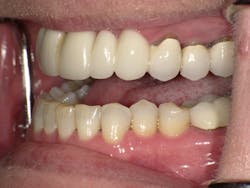

Left side prior to restorative treatment

Karen returned, and under conscious sedation the dentist removed the existing bridge and placed implants as planned. An interim temporary bridge was constructed to get her through the healing process and until abutments would be placed. In the meantime, individual crowns were completed on Nos. 3, 4, and 5. Shortly thereafter, crowns were completed on the left side on teeth Nos. 12, 13, and 14. She is currently awaiting the final implant supported bridge on Nos. 6–8 and 9-11.